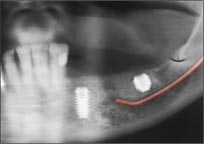

1. 这位可爱的90岁老太太计划在左下植入两个种植体支撑一个桥 (因为对颌是覆盖义齿)。

2. 红色标出的下齿槽神经显示可用的骨高度很有限。

3. 先锋钻备洞之后插入平行杆,可以看出两个骨洞都安全地位于神经管以上。还可以看出来我可以把远中的骨洞再加深1mm。

4. 在骨高度不足的情况下两个种植体都安全地位于下齿槽神经管以上。